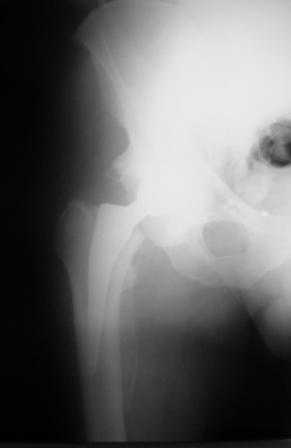

Больной Т. 56 лет, Диагноз: двухсторонний коксартроз 3-4 ст справа, 1-2 ст слева 2.10.08 выполнена операция тотальное бесцементное эндопротезирование. Использовался наружный доступ, положение на боку. Операция протекала без особенностей.

Выполнен послеоперационный ренгеноконтроль в прямой проекции. Рана зажила.

Уважаемый Глеб, предложенные снимки впечатлили! Никто не застрахован...

Приходилось ли кому встречаться с такой ситуацией?Вопросы: вросла ли ножка? Какие могут возникнуть сложности с удалением ножки? Нужна ли будет дополнительная трепанация диафиза? И как? Правильный выбор ножка Corail для ревизии в такой ситуации?

False road это ситуация случается ,в основном у начинающих. Конечно очень неприятно. В этом случае необходимо удалить протез. С удалением в такой срок - месяц-проблем не вижу. Но теперь необходим болле длинный STEM CORAIL. Такой есть у фирмы CORIN .